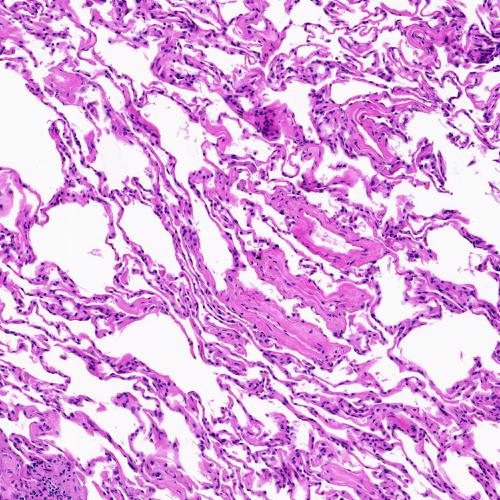

Dataset and Data Preparation – We used the KimiaPath24 dataset to evaluate our experiments. This dataset contain 24 WSIs. The slides show diverse organs and tissue types with different texture patterns [5]. The glass slides were captured by a digital scanner in bright field using a 0.75 NA lens 111TissueScope LE scanner by Huron Digital Pathology. The dataset contains 1325 test images (patches) of size 1000 ×\times 1000 pixels (0.5mm ×\times 0.5mm) from all 24 cases. Fig. 1 shows some example patches (the dataset can be downloaded online222http://kimia.uwaterloo.ca/kimia_lab_data_Path24.html).

Figure 1: Sample patches from KimiaPath24 dataset.